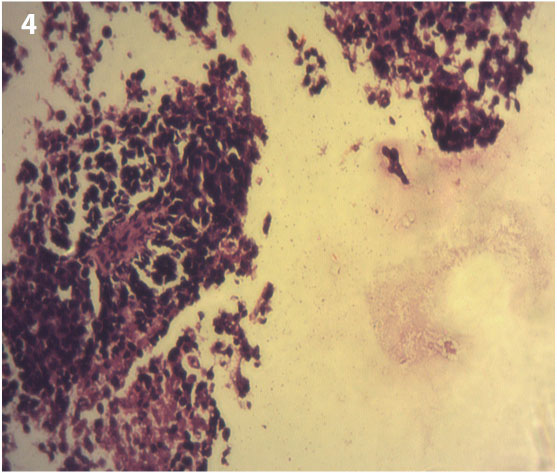

A 5-year-old female child was brought by parents to General Surgery department of Krishna hospital with complaints of fullness in left lower abdomen and swelling over left thigh since last 15 days. Since 15 days patient had fullness in left iliac fossa which rapidly increased in size and was associated with pain. Gradually patient had developed swelling over left thigh [Table/Fig-1]. On general examination patient was well built and nourished and apatite was not reduced only pallor was present. On examination of abdomen there was a palpable mass of 15 X 5 cm in left iliac fossa which was fixed to underlying tissues, hard in consistency. The swelling on the left thigh also was fixed to underlying tissues and hard in consistency. All peripheral pulses were palpable. Based on above findings our clinical diagnosis was mass arising from abdomen and extending into the left thigh. Ultrasonography of abdomen and pelvis suggestive of a large illdefined, isoechoic, solid, retroperitoneal mass [Table/Fig-2] of indeterminate origin in pelvis, posterior to bladder measuring about 112 x 60 x 88 mm in size with fixity to adjacent pelvic vasculature. Few retroperitoneal nodes were enlarged. Computed tomography scan of abdomen suggestive of large, ill defined, lobulated pelvic mass extending to left thigh [Table/Fig-3] causing mass effect with lymphadenopathy. USG guided tru-cut biopsy from abdominal and left thigh mass done which showed malignant small blue round cell tumour [Table/Fig-4]. Immunohistochemistry performed which showed that tumour cells exhibit immunopositivity for myogenin/desmin [Table/Fig-5,6] and are immunonegative for TdT/CD99 [Table/Fig-7,8] which confirmed the diagnosis of Embryonal Rahabdomyosarcoma. As mass was fixed to pelvic vasculatures, it was impossible to operate so patient was refered for chemotherapy and Radiotherapy. Chemotherapy regime VAC (Vincristine, Actinomycine-D and Cyclophosphamide) was started along with Radiotherapy. Last follow up was done after one month and patient was doing well.

Showing microphotograph of biopsy from mass showing multiple blue round tumour cells